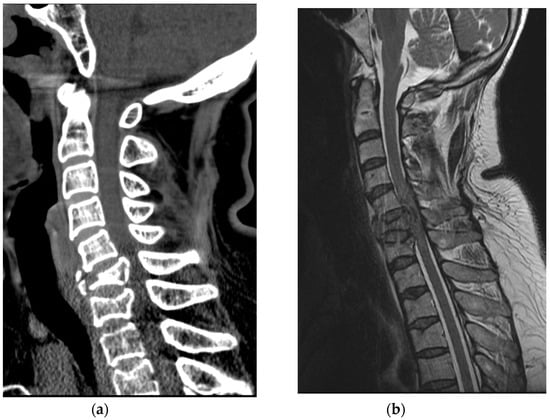

A 50-year-old healthy woman without any relevant medical history went to a nearby park with public outdoor exercise equipment on the morning of 19 October 2019. The patient had been previously active and well before the accident. The patient was working out with the public exercise equipment. While hanging on the inversion table upside down, she slipped and hit her head on the ground. Thereafter, she collapsed and immediately experienced a total loss of motor power in her whole body; she was found at the park and directly transferred to our hospital by ambulance. Computed tomography (CT) brain scan results did not reveal any abnormalities. Cervical spine CT scan showed a bilateral facet dislocation on C5-6 and anterior displacement of the C5 vertebral body (Figure 4a). Cervical spine magnetic resonance imaging (MRI) also showed an anterior displacement of C5 on C6, a complete discoligamentous complex (DLC) injury, which was causing cord compression with extensive edematous cord signal change, and an intramedullary hemorrhage (Figure 4b).

Figure 4. (a) Cervical spine CT revealed facet dislocation at C5-C6 and anterior displacement of the C5 vertebral body; (b) Cervical spine MRI showed cord compression with edematous cord signal change and an intramedullary hemorrhage.